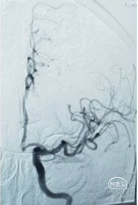

手术DSA: